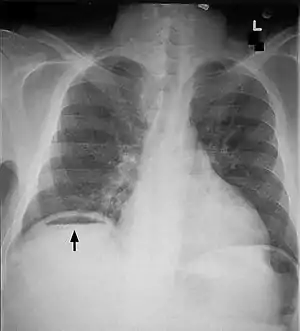

| Frontal chest X-ray. The air bubble below the right hemidiaphragm (on the left of the image) is a pneumoperitoneum. | |

When present, pneumoperitoneum can often be seen on projectional radiography, but small amounts are often missed, and CT scan is nowadays regarded as a criterion standard in the assessment of a pneumoperitoneum.[8] CT can visualize quantities as small as 5 cm³ of air or gas.

Signs that can be seen on projectional radiography are the double wall sign (also called Rigler's sign) and the football sign.

As differential diagnoses, a subphrenic abscess, bowel interposed between diaphragm and liver (Chilaiditi syndrome), and linear atelectasis at the base of the lungs can simulate free air under the diaphragm on a chest X-ray.